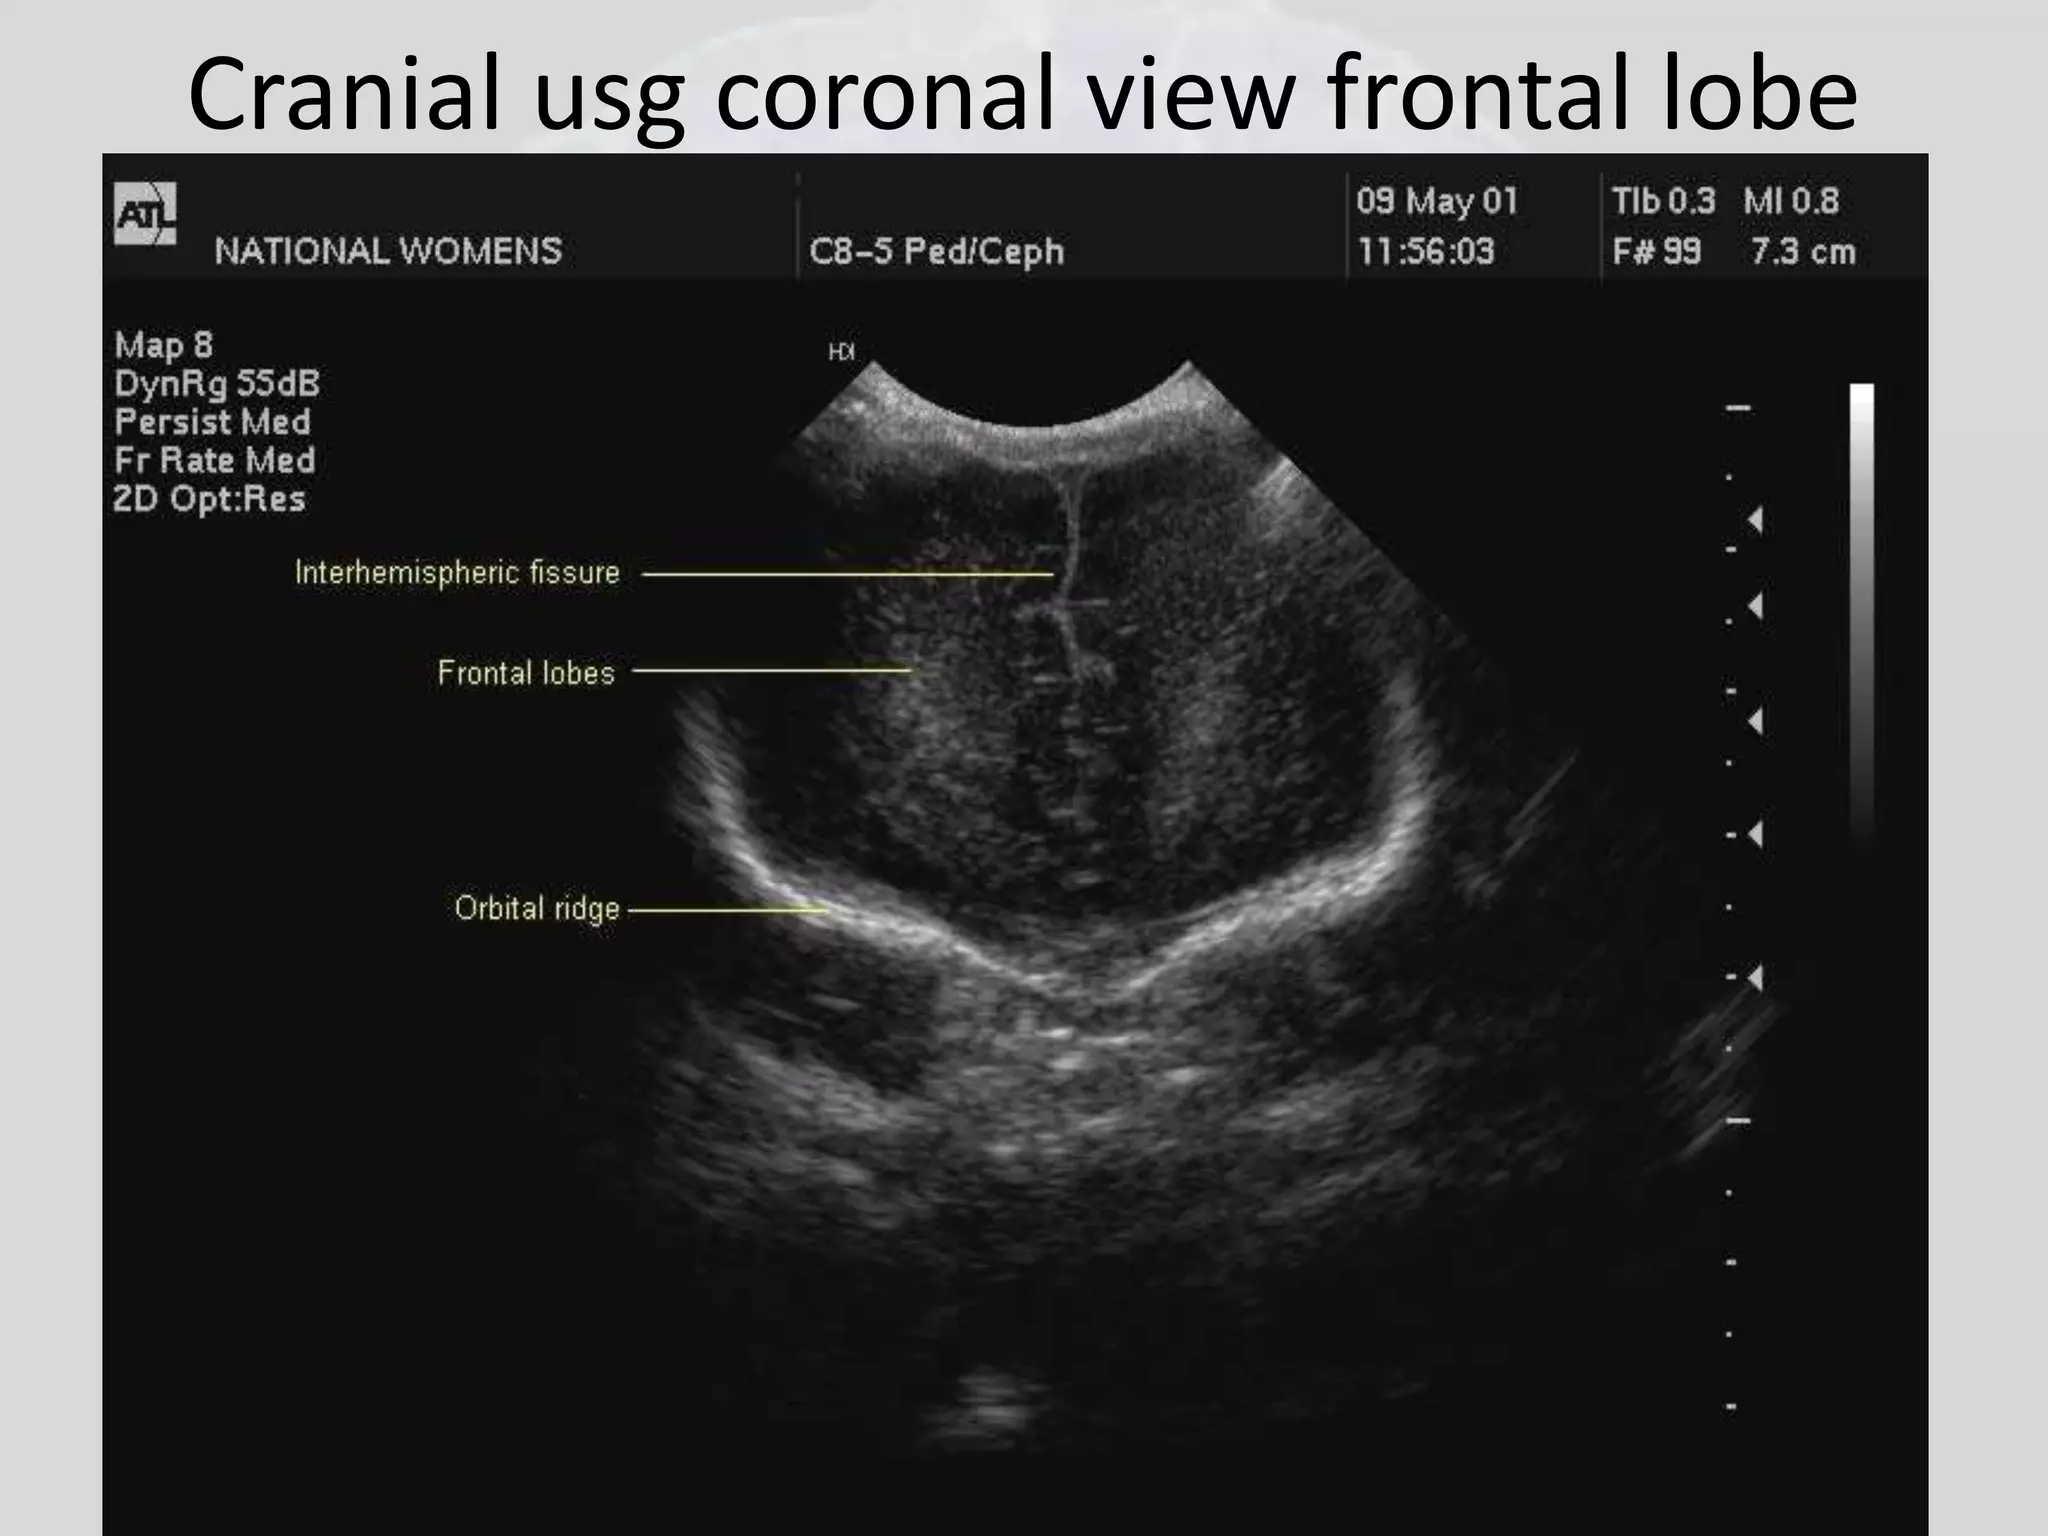

Cranial usg coronal view frontal lobe

Cranial usg coronalview frontal lobe